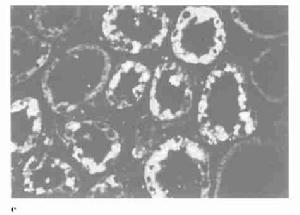

腎乳頭壞死(RenalPapillaryNecrosis,RPN)又稱壞死性乳頭炎或腎髓質壞死,其本質是腎乳頭及其鄰近的腎髓質發生缺血性壞死。本病可發生在多種疾病主要是引起慢性小管間質性腎病的疾病,這些慢性小管間質性腎病時腎臟內髓帶病變常較嚴重。其基本病變是腎臟血循環受損,引起一個或多個腎錐體遠端的局限性或瀰漫性缺血壞死常見臨床表現是在尿路梗阻或嚴重的小管間質性腎病的基礎上發生的發熱、血尿、急性腰痛、尿路絞痛和尿路梗阻少數表現為急性腎功能衰竭、慢性腎功能衰竭或尿濃縮功能損害在部分病例伴有尿路上皮腫瘤在受損的腎乳頭病變有清楚的界限,早期階段見到凝固性壞死這些特點與梗死(infarction)的病理變化非常相似。

乳頭型也叫全乳頭壞死以乳頭的壞死、分界和分離為特點。壞死早期可見乳頭腫脹,黏膜正常,腎盞正常。進行性壞死則使黏膜喪失造影見乳頭不規則,邊沿模糊隨著壞死乳頭的分離,開始形成竇腎盂造影見竇成弧形。當整個壞死乳頭與正常組織分離開時造影可見圍繞竇內壞死乳頭的環形影。在少數病例,壞死乳頭脫落至腎盂,可在尿中發現但在多數病例,壞死的乳頭不脫落,而是被吸收或保持在遠處,之後壞死的乳頭被鈣化或形成結石的核心。如壞死乳頭被吸收或脫落造影可見正常乳頭部位形成“杵狀腎盞”;如壞死乳頭在原處被鈣化,造影可見圍繞竇內壞死乳頭的環形影。脫落的壞死乳頭以及由此形成的結石,可造成尿路梗阻。

腎乳頭壞死的主要發病機制可能是由於各種病因所致的腎髓質血流量不足導致缺血性壞死。如糖尿病引起的微血管病變或鐮狀細胞病引起的血流障礙等。

本病的發生與腎臟髓質錐體血供的解剖生理特點及腎缺血髓質乳頭血管病變與感染有關腎臟血流量的85%~90%分布在皮質髓質僅占10%~15%,越近腎乳頭血供越少且皆源於髓旁腎單位的出球小動脈經直小血管而來受髓質中溶質濃度和滲透壓梯度的影響,血液黏稠度逐漸增高,血流緩慢,是為缺血性壞死的常見部位;伴發的基礎疾病如糖尿病止痛劑腎病、高尿酸血症等本身即可引起慢性間質性腎炎和腎小血管病變,止痛劑腎病、鐮狀細胞性貧血、巨球蛋白血症等致乳頭區受高濃度酸性物質刺激及血液異常高黏滯尿路梗阻時腎盂、腎盞及腎小管內壓增加這些因素均可導致髓質乳頭部嚴重缺血和壞死,兼之病人全身及局部對細菌侵襲易感性增加容易並發腎臟與泌尿道感染進一步加重腎錐體血供障礙和組織壞死。臨床發現約半數以上腎乳頭壞死病例存在兩種或更多(如糖尿病合併尿路感染)的致病因素,易患因素越多,發生率越高。